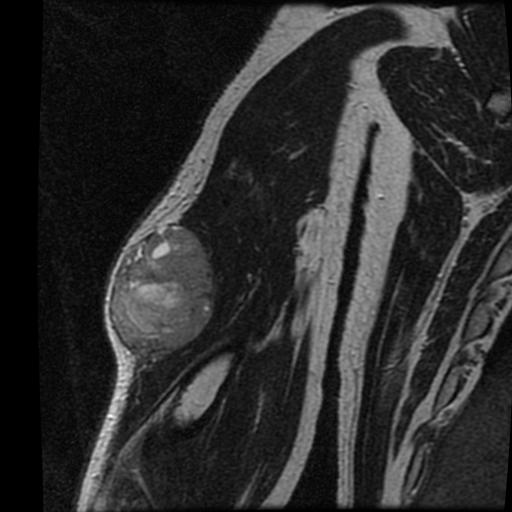

MRI

Anatomy / neurovascular involvement

Sarcoma knee